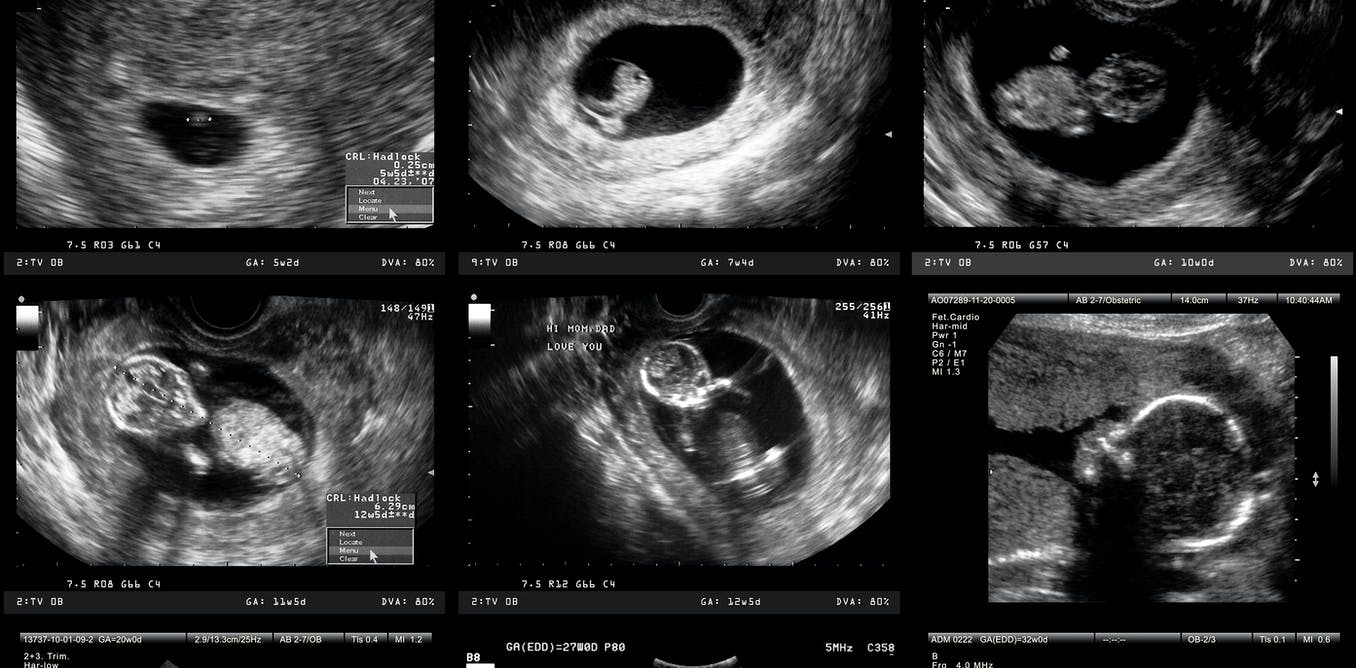

스워스모어 대학(Swarthmore College)의 하워드 A. 슈나이더만 생물학(Howard A. Schneiderman Professor of Biology) 명예 교수인 스콧 길버트(Scott Gilbert)는 발달 생물학 표준 교과서의 저자이다. 그는 생물학적 관점에서 볼 때 모두 인간 생명의 시작점이 될 수 있는 다섯 가지나 되는 발달 단계를 확인했다. 현재 과학이 알고 있는 생물학은 이러한 단계를 구분할 수 있지만 이 단계 중 어느 단계에서 생명이 시작되는지는 결정할 수 없다.

이 단계의 첫 번째 단계는 수정란이 완전한 인간 유전 물질로 형성될 때 난관에서 수정되는 것이다. 그러나 모든 사람의 몸에 있는 거의 모든 세포는 그 사람의 완전한 DNA 서열을 가지고 있다. 만약 유전 물질만으로도 잠재적인 인간이 될 수 있다면, 우리가 항상 그렇듯이 피부 세포를 흘리는 순간 우리는 잠재적인 인간을 잘라내고 있는 것이다.

두 번째 그럴듯한 단계는 수정 후 약 2주에 발생하는 장배 형성(gasstrulation)**이라고 한다. 그 시점에서 배아는 일란성쌍둥이 또는 세 쌍둥이 또는 그 이상을 형성하는 능력을 잃는다. 따라서 배아는 생물학적 개체가 되지만 반드시 인간 개체는 아니다.

세 번째 가능한 단계는 태아의 뇌에서 인간 특유의 뇌파 패턴이 나타나는 임신 24~27주이다. 이 패턴이 사라지는 것은 인간 사망에 대한 법적 기준의 일부이다. 대칭적으로 말하면, 아마도 그 모습은 인간 생명의 시작을 표시하는 것으로 간주될 수 있다.

네 번째 가능한 단계는 미국에서 낙태를 합법화한 로 대 웨이드(Roe v. Wade) 판결에서 인정된 것으로, 태아가 일반적으로 이용 가능한 의료 기술의 도움으로 자궁 밖에서 생존할 수 있게 되는 생존 가능성이다. 오늘날 우리가 가진 기술로 그 단계는 약 24주이다.

마지막 가능성은 탄생 그 자체이다.